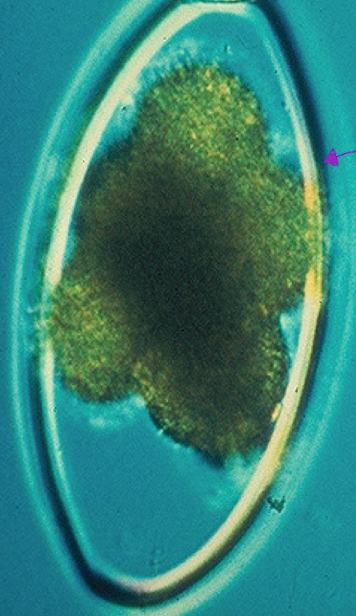

nematodirus- very large strongyle-type egg